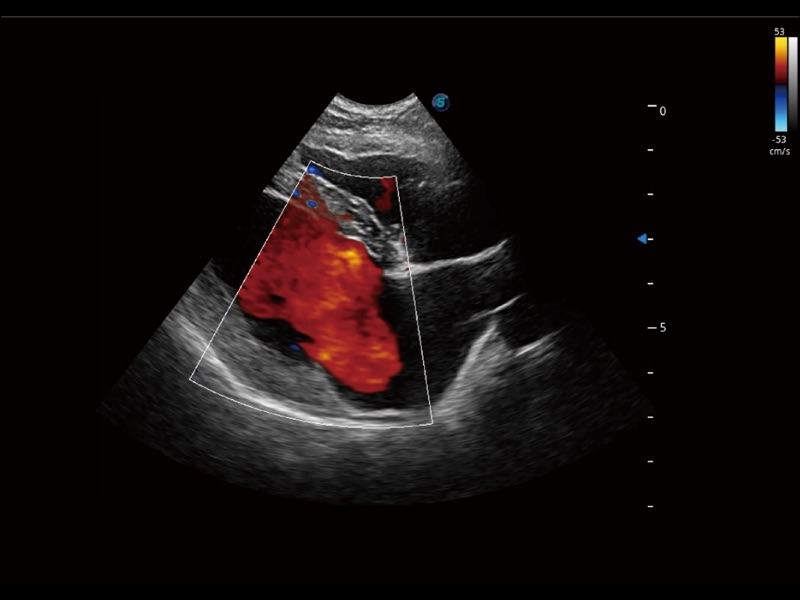

采用红、橙、黄、绿、青、蓝、紫这七种肉眼最为敏感的色彩,直观地显示组织内血流灌注的时间先后信息,更精准捕捉血流灌注走行细节。

通过创新的 Matrix E自适应滤波器和超长时间域算法,极大提升超低速微细血流的检出能力,同时更精准地滤除软组织和噪声信号,为兽用医生提供以往无法通过常规血流获得的疾病诊断信息。

通过色彩血流和实时宽景相结合,可观察到完整的静脉或动脉的血流,方便医生检查。实时扫查过程中,如有任何操作失误也可以很容易地进行回扫擦除,而不会中断扫查。